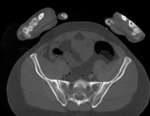

Input

this is the main fixed reference image. All images are ev. aligned into this space lleft this is the moving image

baseline image follow-up

• fixed: CT , 0.6 x 0.6 x 0.40 mm voxel size, axial; 292 x 292 x 91 unsigned short image

• moving: CT , 0.6 x 0.6 x 0.40 mm voxel size, axial; 512 x 512 x 107 unsigned short image